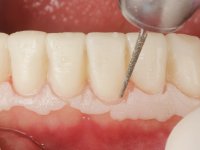

Realizado o diagnóstico e tomada a decisão quanto ao tratamento a executar, tornou-se importante definir qual a sequência de trabalho a adotar no sentido de conseguir a reabilitação da D.V.O. (V.D.O), de forma progressiva e equilibrada. Na primeira fase fez-se uma pré-impressão da arcada inferior com silicone tipo “putty” e em seguida realizou-se o preparo dentário de todo o sector posterior. O preparo para os overlays foi feito coronalmente à linha amelo cementaria no sentido de ser o mais conservador possível. A impressão foi feita com técnica de dupla mistura após afastamento gengival realizado com pasta de caulino. A provisória foi realizada com resina composta de polimerização dual. Em laboratório foram realizados os overlays após se ter aberto ligeiramente (1,5mm) a D.V.O. nos modelos montados em articulador semi-ajustável. Simultaneamente o sector antero-inferior foi encerado no sentido de acompanhar este aumento da D.V.O. Também foi confecionada uma chave de silicone translucido para posterior confeção dos provisórios antero-inferiores. Em boca foi primeiro realizada a provisionalização dos dentes anteriores utilizando resina composta previamente aquecida após preparação das superfícies dentárias para a adesão. Foi colocado o dique de borracha para promover o isolamento absoluto e posteriormente foram colados os overlays. Em laboratório foi realizada nova chave de silicone para confecionar os provisórios antero-superiores. Seguidamente em boca foram preparados os seis dentes antero-superiores após colocação do fio de afastamento gengival. Feita a preparação adequada das superfícies dentárias foi realizada a impressão com técnica de dupla mistura e a respetiva provisória. Em laboratório foram confecionadas 6 facetas feldespáticas num modelo de trabalho tipo “Geller”. A provisória foi removida e as facetas foram coladas em boca utilizando um isolamento relativo competente. Esta opção foi tomada em virtude de uma prévia experiencia negativa com a colocação do dique de borracha na mandibula. Após a colagem dos laminados antero-superiores foram dadas 12 semanas para avaliar a adaptação do paciente à nova situação e então iniciar a confeção das facetas antero-inferiores. Após colocação do fio de afastamento gengival. foram feitos os preparos dentários adequados e em seguida foi feita a impressão. Também foi feita a preparação do dente 3.4 que, entretanto, tinha sofrido uma fratura do overlay. As facetas e a restauração do 3.4 foram realizadas num modelo de trabalho tipo “Geller”. Após remoção da provisória, as facetas foram coladas em boca, utilizando um isolamento relativo pelas razões apontadas anteriormente. Após colocação do trabalho o paciente foi reabilitado por outros colegas com um implante na zona do 2.6 e substituição da coroa aparafusada sobre o implante colocado no local do 3.5. Posteriormente surgiram fraturas nos overlays dos dentes 4.7 e 3.7 que foram reabilitados com overlays em Zr.